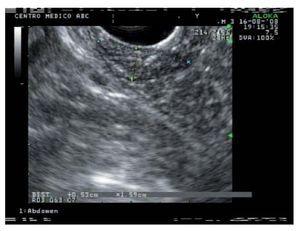

Varón de 63 años de edad con antecedente de esófago de Barrett sin displasia. Durante el estudio endoscópico de seguimiento se identificó una lesión polipoide, ovalada, de alrededor de 20 x 15 mm, sésil y de aspecto digitiforme en la segunda porción del duodeno originada en el ámpula de Vater. Se tomaron múltiples muestras para biopsia de esta lesión (Figura 1). El estudio patológico informó adenoma tubulovelloso negativo para enfermedad maligna. Se realizó ultrasonido endoscópico (Olympus GFUCT140, Aloka alfa 5), que mostró una lesión con ecogenicidad mixta, de predominio hiperecógeno, de cerca de 30 mm, que sólo afectaba mucosa y submucosa (Figura 2). No se observó invasión al colédoco ni el conducto pancreático y tampoco se identificaron adenopatías.

Figura 2. Vista endosonográfica desde la segunda porción del duodeno de una lesión periampular que muestra invasión hasta la submucosa y muscular propia intacta.